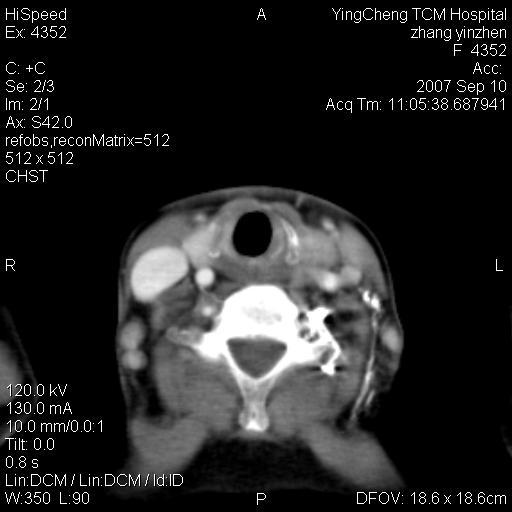

以下是引用夏季在2007-9-18 11:00:00的发言:[br]1。右肺肿块,周围有短毛刺,肺门侧有血管与其相连,胸壁侧有胸膜凹陷征,考虑周围性肺癌 2。左侧甲状腺软组织肿块,内有高密度钙化灶,考虑左侧甲状腺腺瘤。